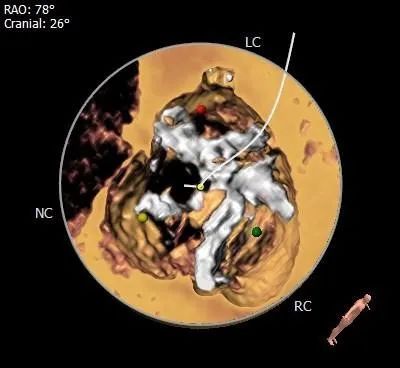

冠脉评估:

冠脉开口高度可,左冠瓣叶长于开口下缘到附着点距离。

钙化评估:

重度钙化,集中分布于左冠窦、右冠窦内。